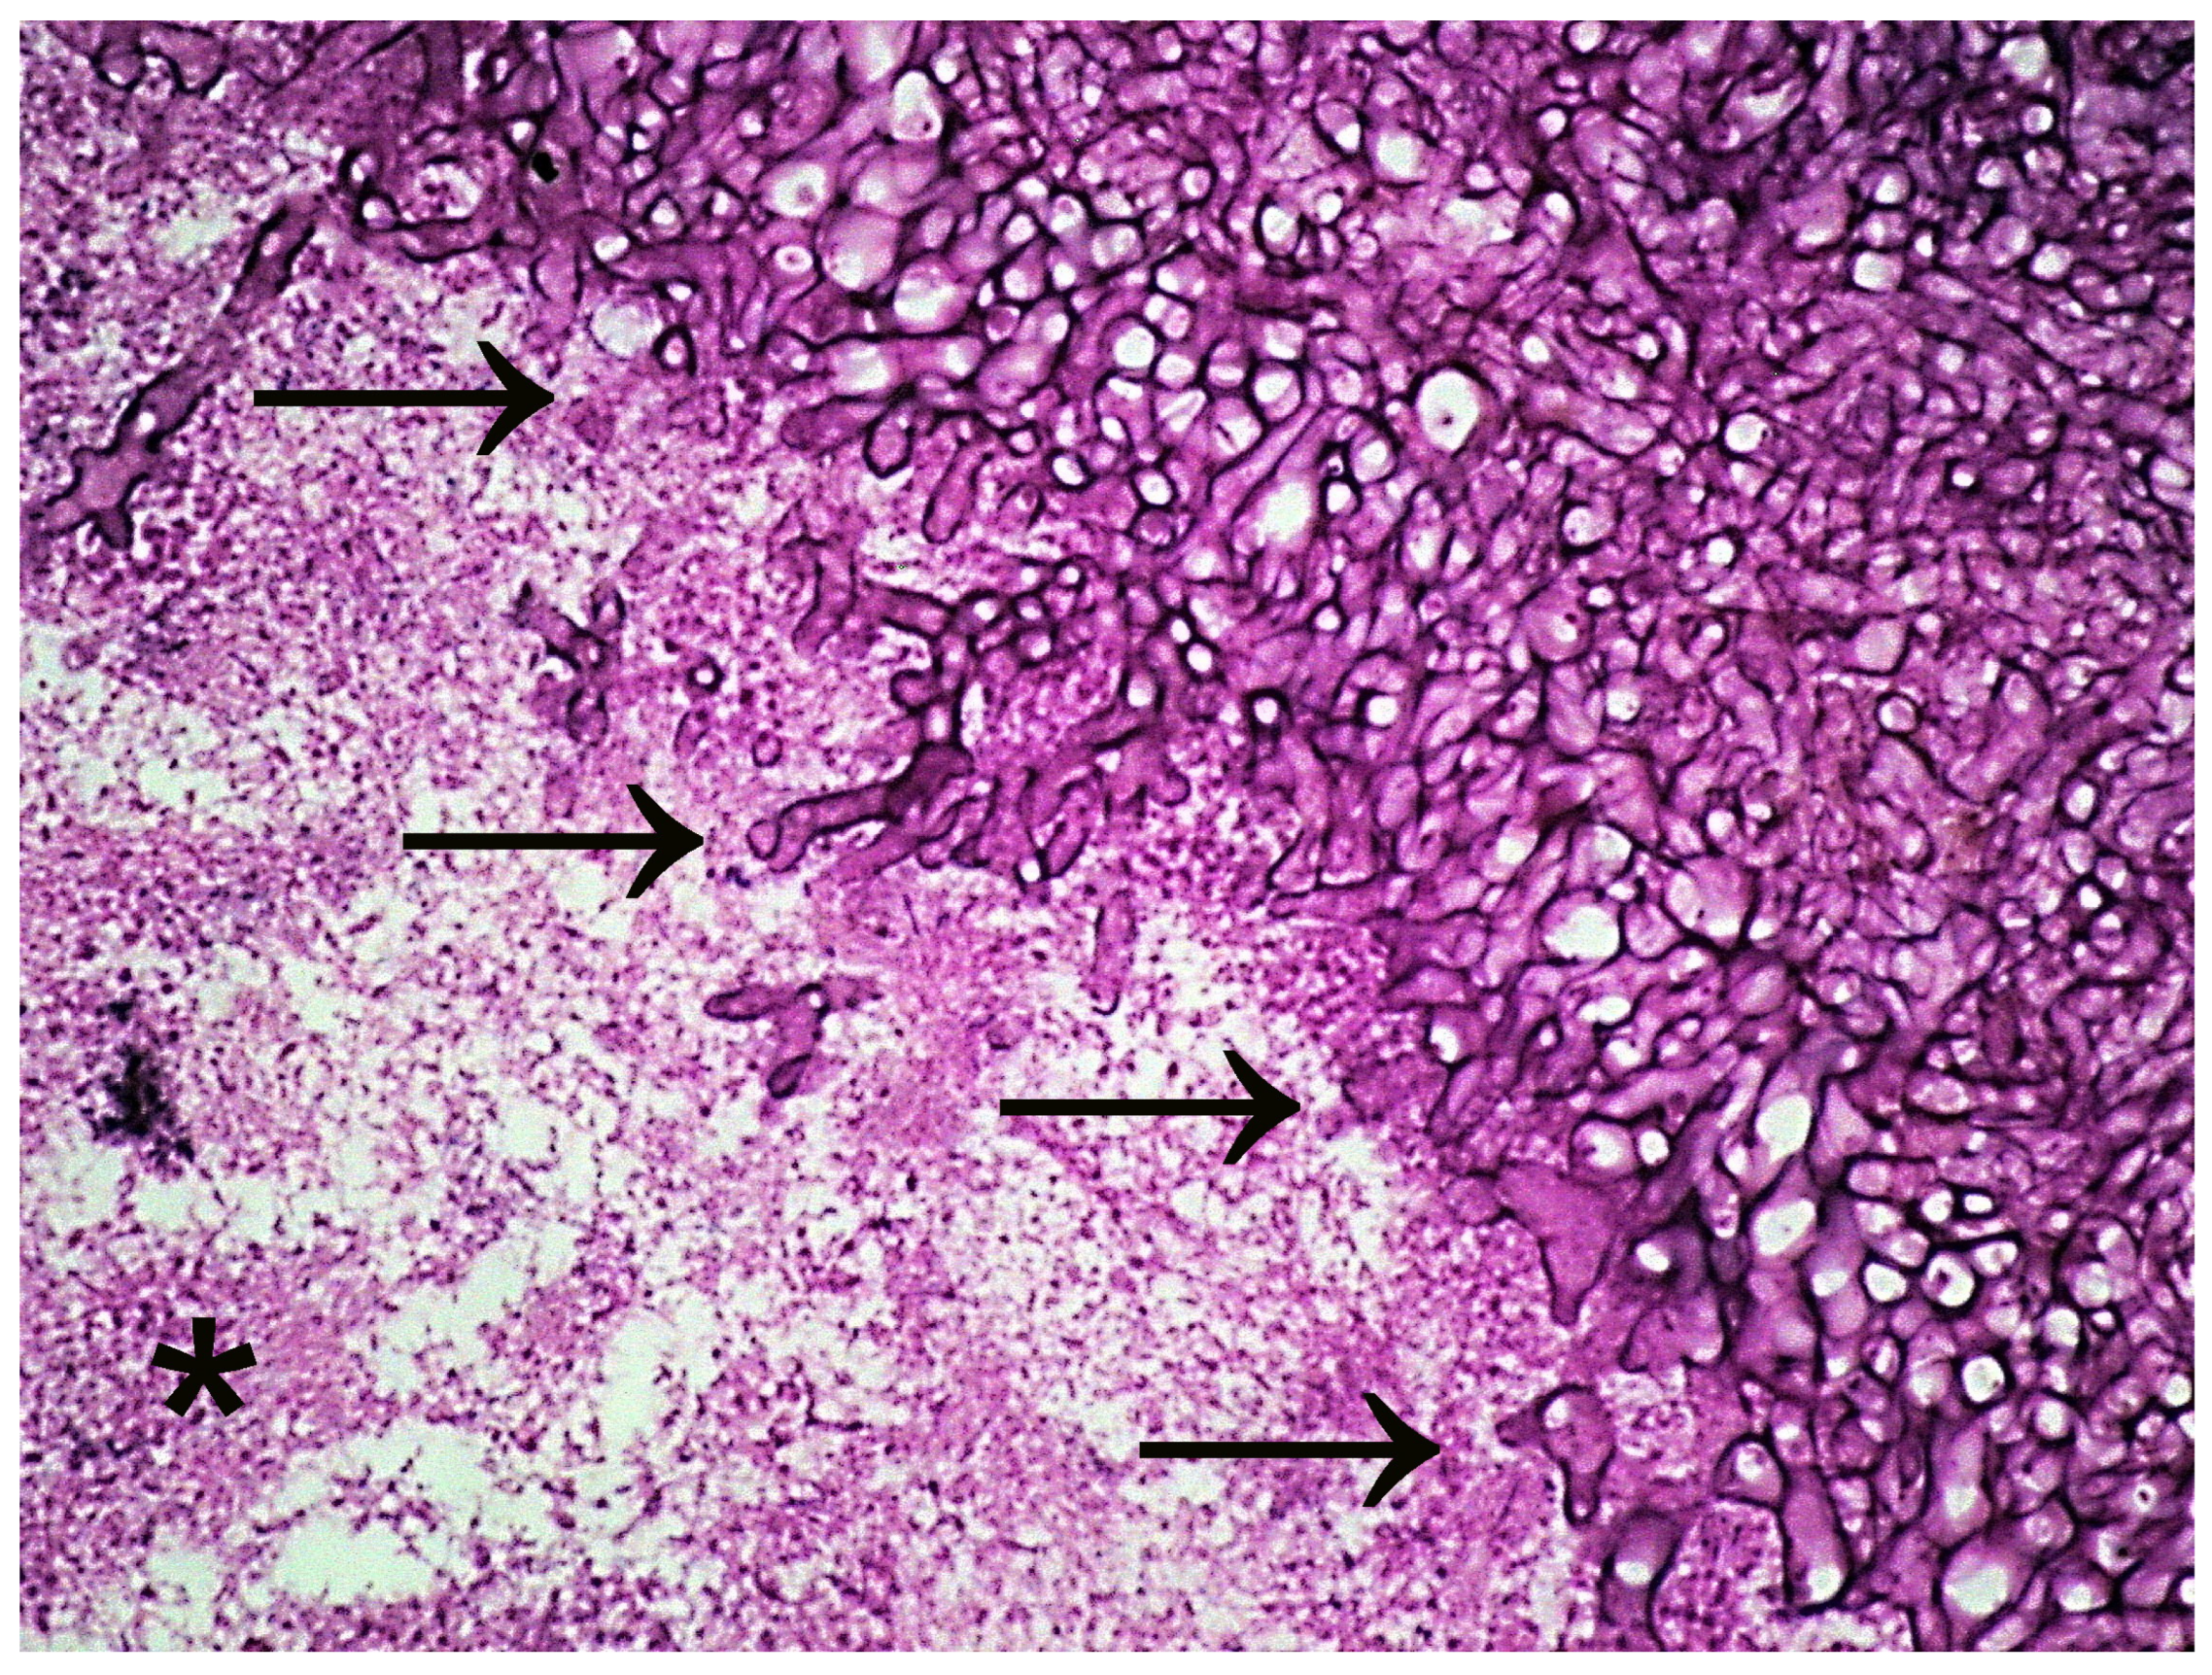

- Zhong, M.; Xiong, Y.; Zhao, J.; Gao, Z.; Ma, J.; Wu, Z.; Song, Y.; Hong, X. Candida albicans disorder is associated with gastric carcinogenesis. Theranostics 2021, 11, 4945–4956. [Google Scholar] [CrossRef]

| Gastric cancer | An imbalance in fungal communities with changes in fungal composition and a large increase in the abundance of C. albicans leads to gastric cancer. | The increase in C. albicans is involved in the decrease in the abundance and diversity of other gastric fungi. | [30] |